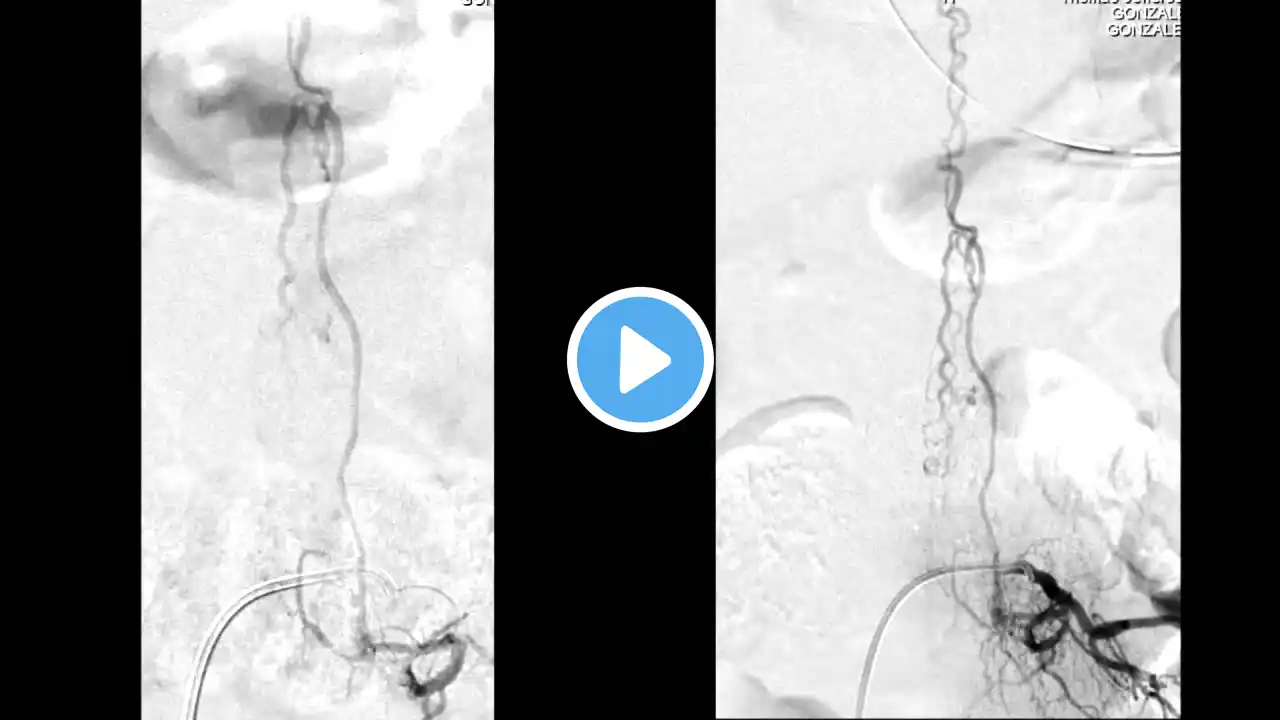

Spinal hemangioblastoma embolisation

Spinal DSA and PVA particle embolisation of a spinal hemangioblastoma with holocord syrinx